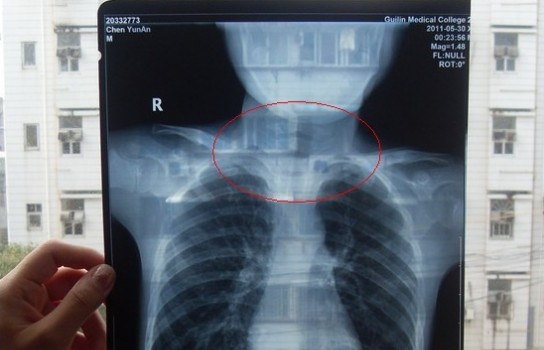

胸部正位X光片圖

可是,陳先生的一次偶然發現,讓他們一家過上了提心吊膽的日子。因為,在安安出院一個月后,陳先生偶然翻出孩子治療期間的X光片。發現在X光片中,孩子的生殖器官以及甲狀腺等敏感部位也在被放射區域中。而陳先生上網查到:人體拍攝X光片是有一定輻射的,并且輻射有可能引起基因變異等問題,他立馬陷入恐慌中。

至于,為什么拍攝X光時,孩子的敏感部位也在放射區域內,這讓陳先生百思不得其解。為此,他專門到醫學院進行了質疑。而醫院的醫務人員說,拍腹部X光片就要照到睪丸,要檢查睪丸是否正常,而且怕小孩亂動,所以要照寬些。